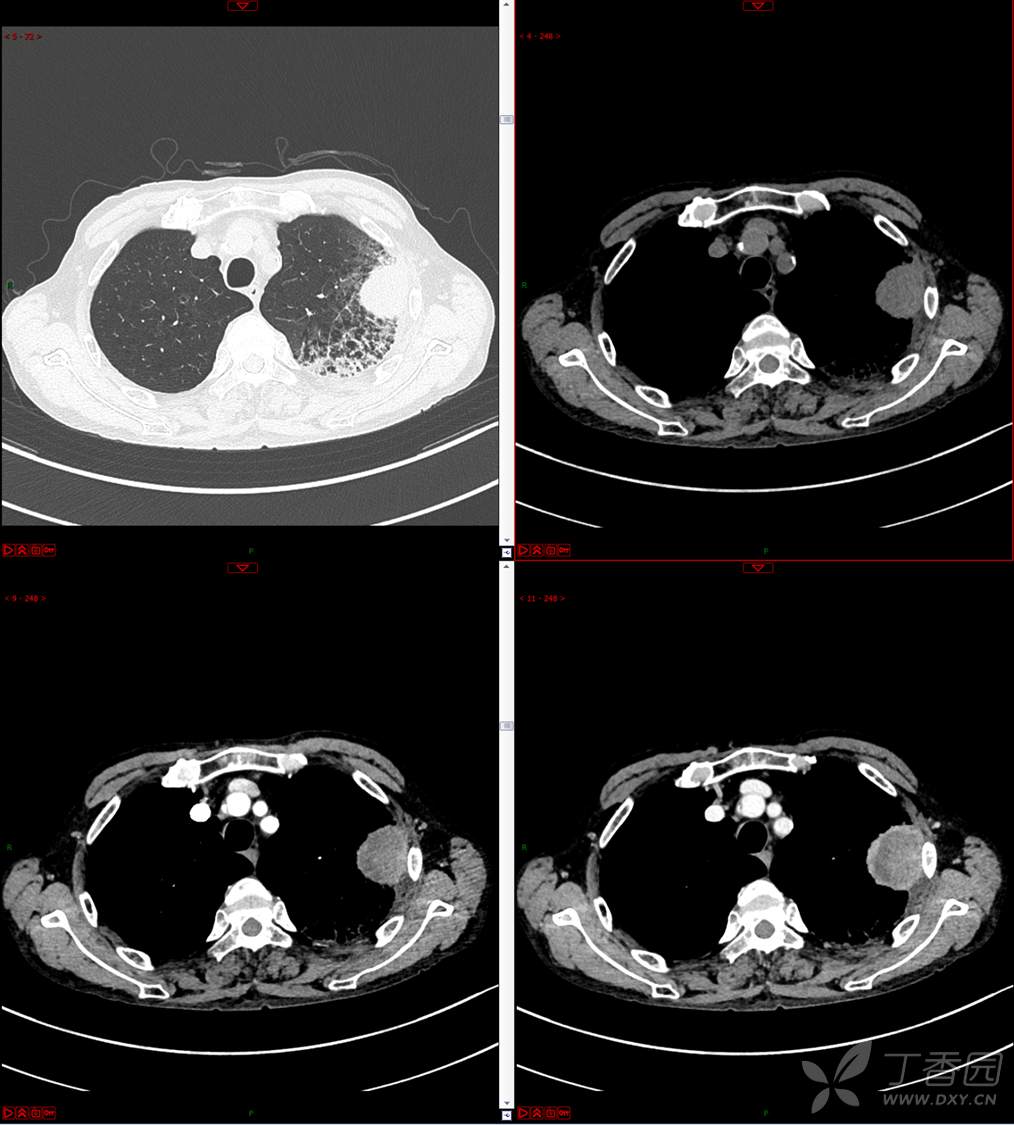

现病史:患者自诉5月前无明显原因及诱因出现纳差、乏力,伴进食后腹胀,无腹痛、腹泻、发热、盗汗、恶心、胸闷,未行特殊处理。1月前无明显原因诱因出现咳嗽,呈阵发性,咳白痰,痰中带鲜红色血丝,10余口/日,无血块,仍伴纳差、乏力、进食后腹胀,无恶心、呕吐、呕血,无头晕、心慌、喘憋、胸闷。在家未行特殊治疗,来我院就诊,2022.8.18行胸部(肺)CT平扫:左上肺占位并左侧肋骨骨质破坏,考虑间叶源性恶性肿瘤。门诊以“肺肿物”收入我科。患者自发病以来,神志清,精神可,饮食差,睡眠可,二便正常,近3月减轻5Kg。